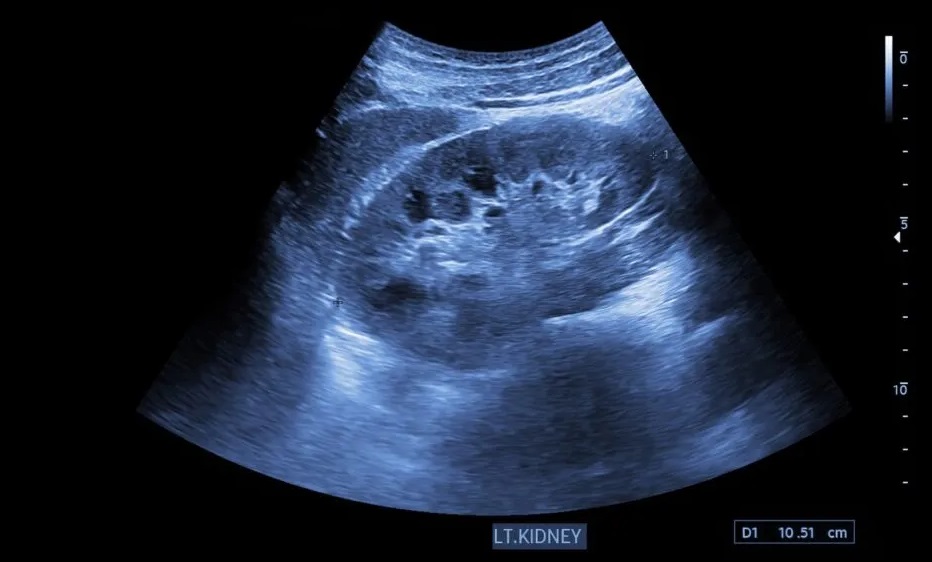

अल्ट्रासाउंड: शरीर की ज्योग्राफी का नक्शा

डॉक्टर अल्ट्रासाउंड कराने पर जोर इसलिए देते हैं क्योंकि यह वह जानकारी देता है जो ब्लड टेस्ट कभी नहीं दे सकता। अल्ट्रासाउंड से पथरी की संख्या (Number), आकार (Size) और जगह (Location) का साफ पता चलता है। कई बार छोटी पथरी भी पेशाब का रास्ता रोक देती है जिससे किडनी में पेशाब भरने लगता है और सूजन आ जाती है। इसे अल्ट्रासाउंड के जरिए तुरंत पकड़ा जा सकता है। यदि रुकावट का समय पर पता न चले तो किडनी हमेशा के लिए डैमेज हो सकती है।